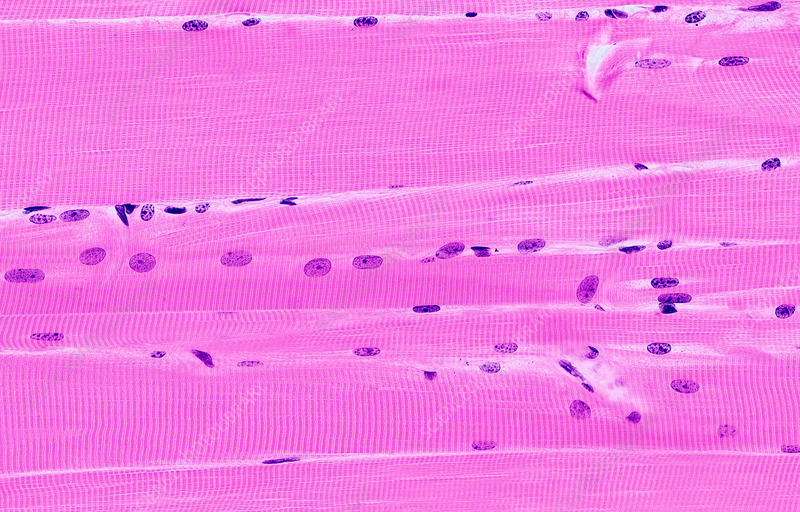

Skeletal Muscle

knowt flashcard image